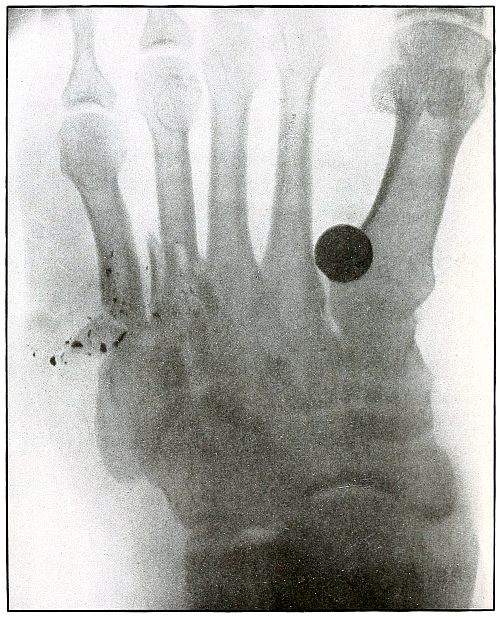

154. Gunshot wound, foot 318

155. Gunshot wound, foot 320

156. Gunshot wound, foot, multiple 322